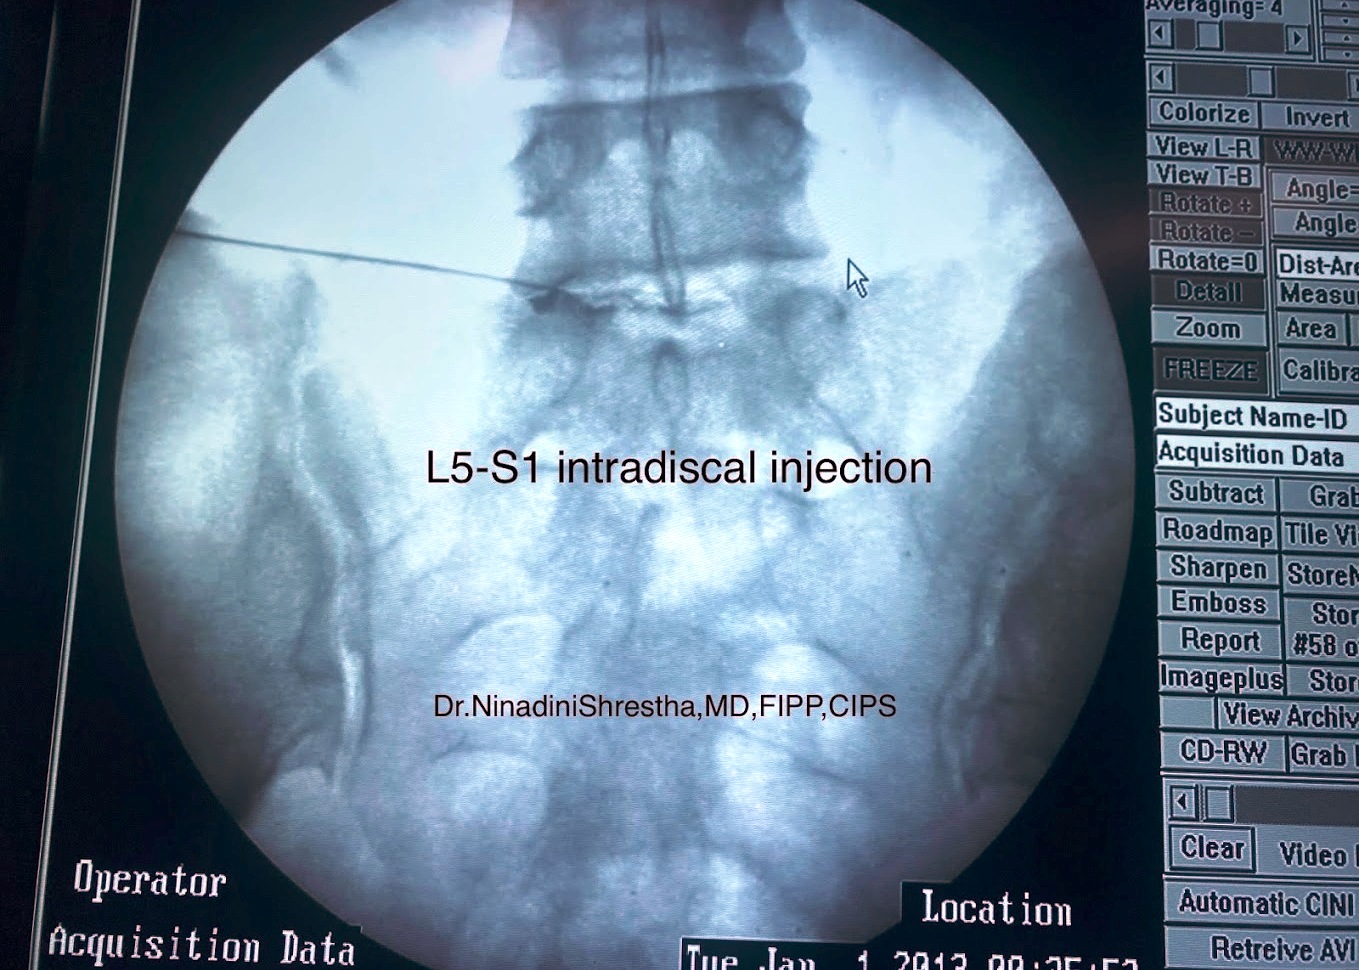

As a compassionate and highly skilled pain management specialist, Dr. Ninadini is committed to the precise diagnosis and multidisciplinary treatment of various pain syndromes. Whether you are coping with chronic back pain, osteoarthritis, or post-operative neuropathic pain, she employs cutting-edge interventional techniques alongside personalized care to deliver optimal therapeutic outcomes.

What is the role of interventional procedures in pain management?

Interventional procedures, such as nerve blocks, radiofrequency ablation, and spinal cord stimulation, play a crucial role in managing chronic pain conditions. These minimally invasive techniques target the source of pain and are often used when conservative treatments are insufficient, providing significant relief and improving the quality of life.